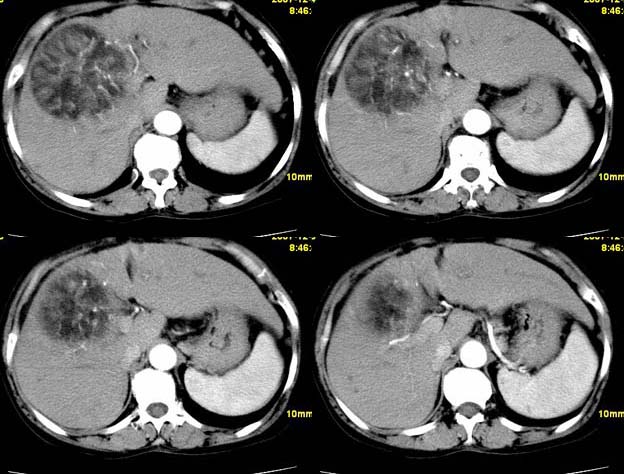

增强

肝癌(巨块型)。

肝细胞癌偶尔也会出现脂肪变性。

肝血管平滑肌脂肪瘤可能性大;原发型肝癌待排。